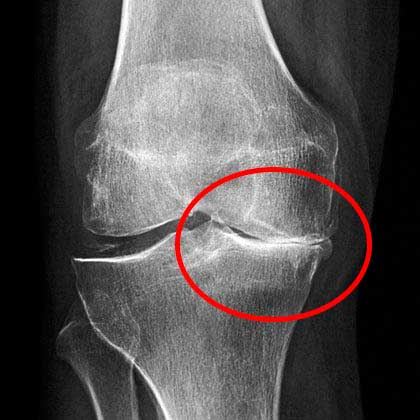

Kondisi lutut saya kala itu. Rasa sakit yang kuat

Di rumah sakit, dokter mengamati hasil rontgen saya cukup lama sebelum akhirnya memberi tahu bahwa saya tidak boleh lagi melakukan pekerjaan fisik berat atau mengangkat beban lebih dari 2 kilogram.

X-ray menunjukkan masalah serius dengan lutut saya